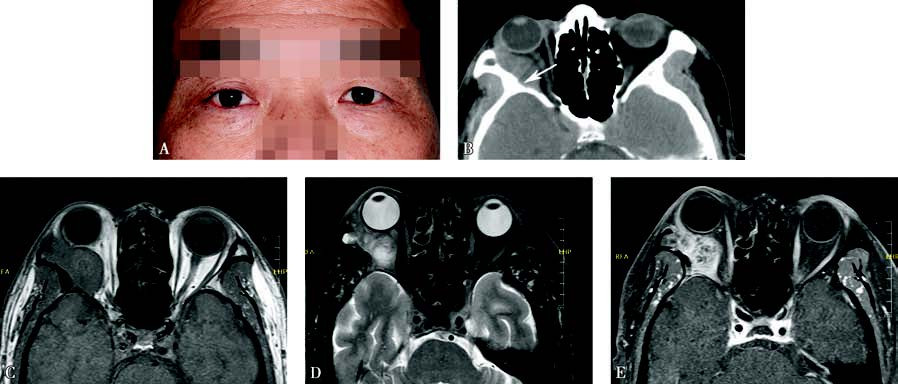

Figure 1 Appearance and imaging of adenoid cystic carcinoma of the lacrimal gland

A. A photograph of a patient with adenoid cystic carcinoma of the right lacrimal gland, showing proptosis of the right eye.

B. Axial CT imaging demonstrates a hyperdense mass in the extraconal space posterior to the globe, extending along the orbital walls toward the orbital apex and associated with bone destruction (white arrow).

C. MRI T1-weighted imaging shows an isointense signal from the tumor.

D. MRI T2-weighted imaging with fat suppression reveals inhomogeneous tumor signals.

E. Contrast-enhanced T1-weighted imaging demonstrates inhomogeneous enhancement of the tumor.